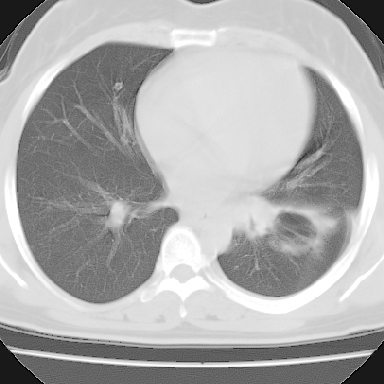

支持。另外,双侧腋下似见增大淋巴结影,有侧乳腺4、5点处皮下高密度结节影是什么?食管中下段有没有问题?病人比较年轻,因此诊断恶性肿瘤要慎重,多结合临床和其他检查,多考虑一些,也可短期抗炎治疗后复查。

左下肺有空洞,壁厚薄不均,壁结节,两肺多发小结节影,腋窝下可疑淋巴结肿大,综上所述考虑周围性肺癌并两肺转移可能性大,建议穿刺活检。

右肺多发小结节影,边界清楚,符合转移瘤的特点;2、左下肺偏心性空洞影,右侧乳腺内高密度影,需要查体除外右侧乳腺肿瘤;3、腋窝淋巴结肿大,考虑转移。

支持癌性空洞:壁厚,无液平,内壁不规则,外壁呈分叶状,较大,偏心性,壁结节,胸膜凹陷,转移灶。

1、癌性空洞,右肺小结节考虑转移。2、曲霉菌感染?右侧为播散